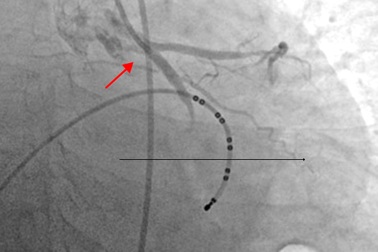

Cẩn trọng cơn đau ngực cấp tính báo động bệnh mạch vành nguy hiểmBệnh nhân 69 tuổi (Thường Tín, Hà Nội) đang ngồi bỗng dưng lên cơn đau ngực dữ dội. Khi gia đình đưa đến viện, bệnh nhân được chụp động mạch vành, phát hiện tổn thương xơ vữa gây tắc mạch, đã phải đặt stent để "thông" dòng chảy thông thoáng cho mạch vành.

Cứu sống bệnh nhân ngừng tim 60 phútCó cơn đau ngực trái, nữ bệnh nhân vào viện, được chẩn đoán nhồi máu cơ tim cấp, can thiệp stent động mạch vành. Theo dõi tại phòng sau can thiệp, bệnh nhân đột ngột mất ý thức, ngừng tuần hoàn.